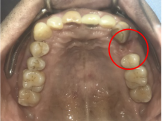

レントゲンで詳しく診てみると、虫歯が歯根のほうまで進行し、保存することができないことがわかり、抜歯しました。抜歯後、骨が大きく欠損していましたので、骨造成を行いインプラントを2本埋入しました。

Before

【抜歯後】